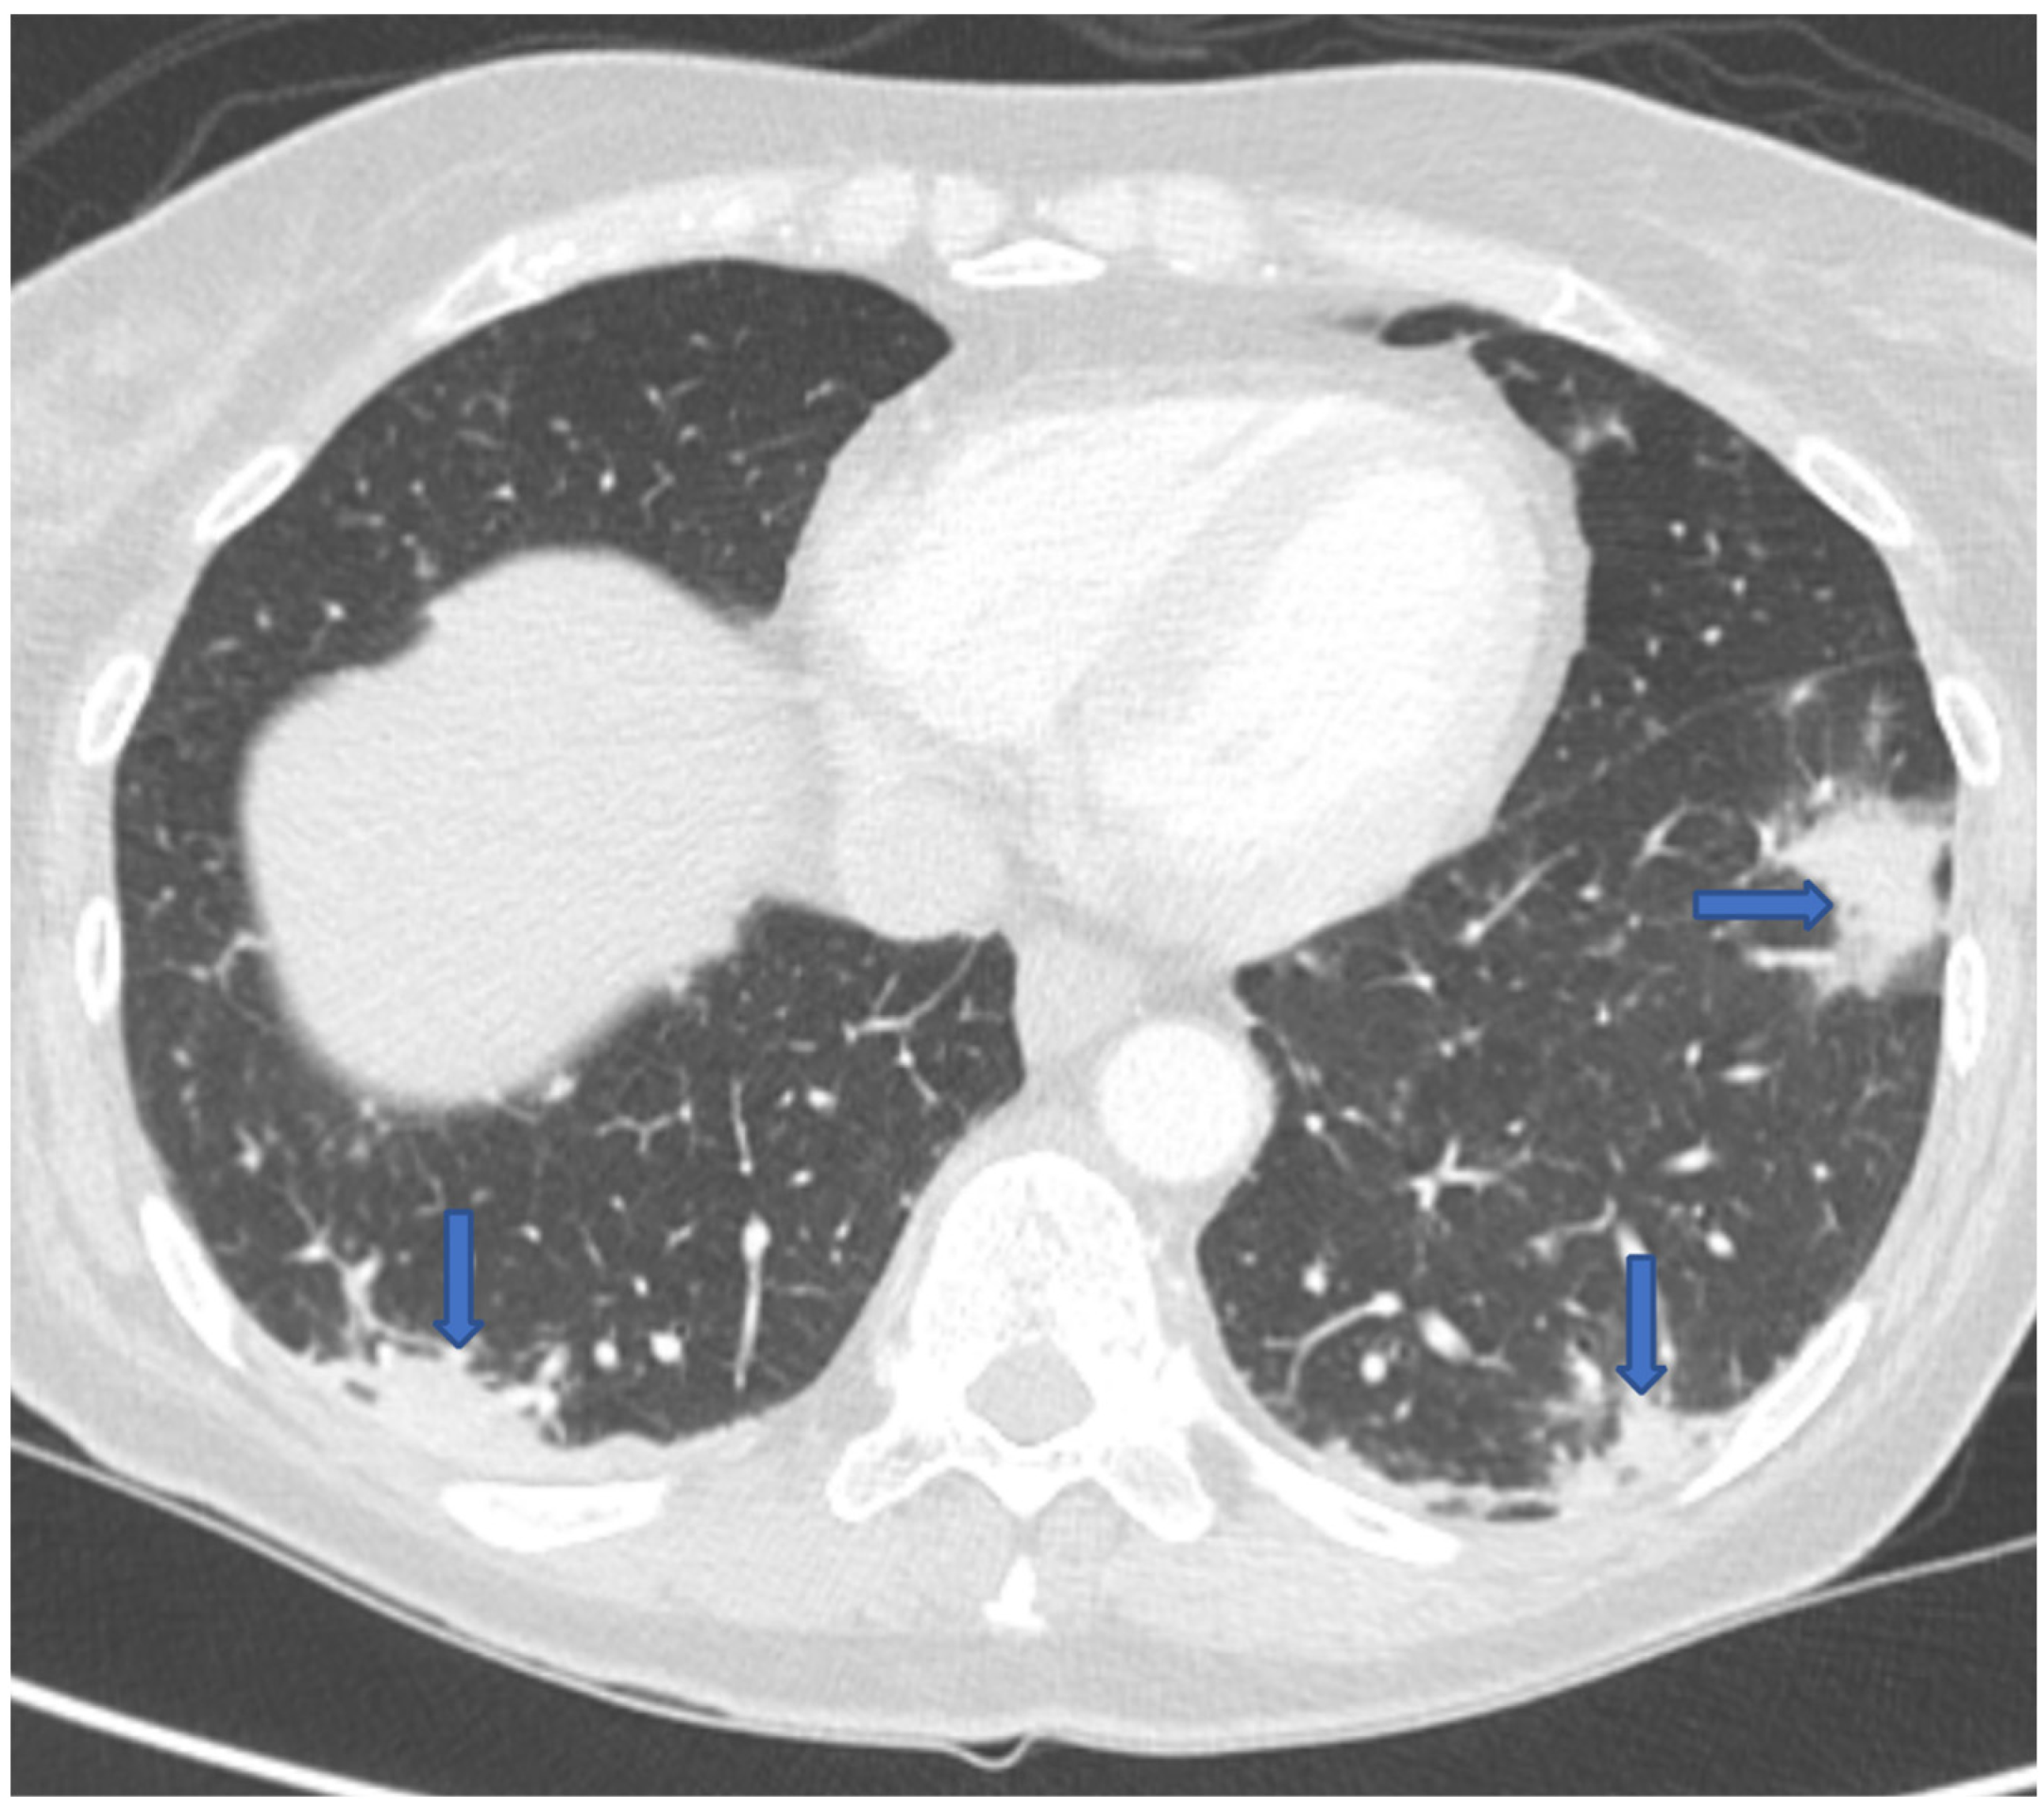

Eighteen months following her transplant, she went to her local hospital in Montana with 3 months of progressive fatigue, 2 weeks of dyspnea and dry cough, and recent onset of drenching night sweats and headaches. She had been off immunosuppression for 6 months and anti-coccidioidal prophylaxis for 3 months. A chest computed tomography (CT) scan revealed bilateral ground-glass and nodular lung opacities in a peripheral distribution (Figure 1). She was diagnosed with a community acquired pneumonia and discharged home on oral azithromycin. A few days after homegoing, the patient developed an erythematous maculopapular rash over her face and arms, thought to be an allergic reaction. Since the patient had no improvement in her symptoms, she decided to travel to our institution for further care.

Figure 1. CT chest revealing multifocal bilateral peripheral opacities.